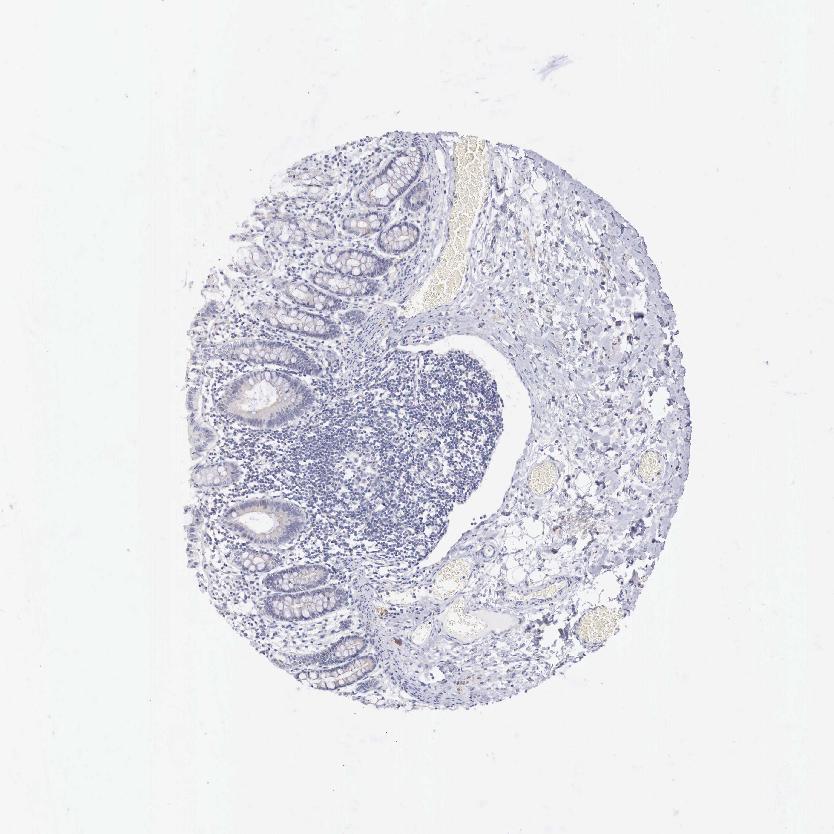

COLON - Antibody stainingi

Antibody staining in the annotated cell types in the current human tissue is reported as not detected, low, medium, or high, based on conventional immunohistochemistry profiling in selected tissues. This score is based on the combination of the staining intensity and fraction of stained cells.

Each image is clickable and will lead to virtual microscopy that enables deeper exploration of all samples and also displays staining intensity scores, fraction scores and subcellular localization as well as patient and tissue information for each sample.

Antibody HPA000367

Endothelial cells Not detected

Glandular cells Not detected

Peripheral nerve/ganglion Medium